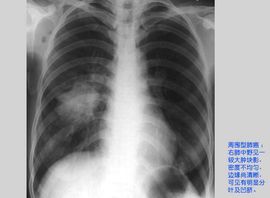

1.2 X線檢查:異常的胸部X線表現常是結節病的首要發現,約有90%以上患者伴有胸片的改變。目前普通X線片對結節病的分期仍未統一。1961年,Scandding將結節病分為四期(1~4期),近年又將其分為五期(0,1~4期)。而目前較為常用的仍是Siltzbach分期,國內亦採用此分類方法。

122 Ⅰ期 兩側肺門和(或)縱隔淋巴結腫大,常伴右氣管旁淋巴結腫大,約占51%。